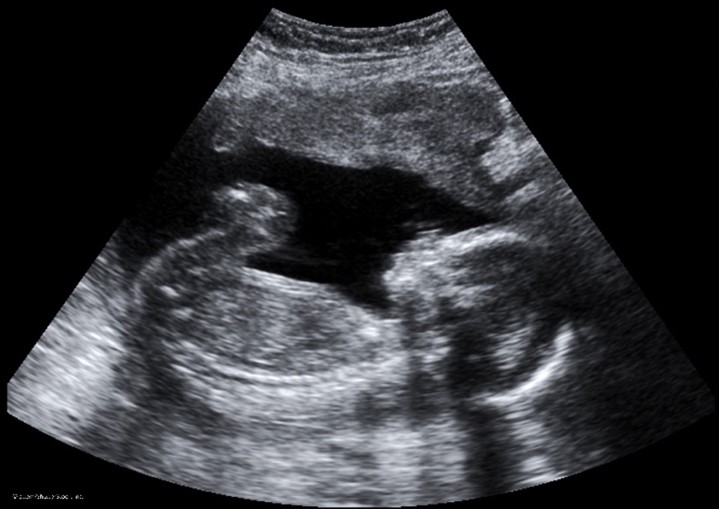

Conventional ultrasound displays images in flat sections of the body. However, technological advancements have led to the development of an ultrasound that allows formatting sound wave data into 3-D images. The most widespread use of a 3-D ultrasound is to assess a developing fetus, and the distinction between the resultant images generated from a conventional sonogram versus a 3-D sonogram is demonstrated in Figure 7. A 4-D ultrasound can also be used to assess fetal characteristics. A 4-D ultrasound is a 3-D ultrasound that is put into motion (FDA, 2020).

Figure 7

Conventional Sonogram (left) Compared to 3-D Sonogram of Fetus (right)